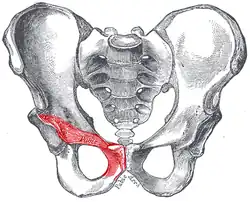

Stydká kost lidské pánve u muže. Gray's Anatomy, 1918 | |

Stydká kost (latinsky: os pubis) je jedna ze tří kostí tvořících pánevní kost. Podkládá pánevní dno, tvoří ohraničení ucpaného otvoru a část jamky kyčelního kloubu.

Stejně jako ostatní pánevní kosti je i stydká kost párová. Dvě protilehlé kosti jsou přiloženy k sobě a spojené chrupavčitou stydkou sponou (symphysis pubica) a vazivem. To, že spojení mezi kostmi není zkostnatělé, je důležité zvláště u žen, při porodu se vlivem hormonů chrupavka mírně povolí a umožní tak roztažení pánve a snazší porod.